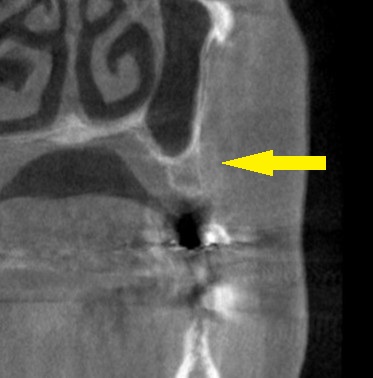

CT撮影してみると、下の写真左のように、骨の幅は5mm程度、高さは6mm程度と、インプラント埋入には不十分でした。

そこで、上方には患者様ご自身の骨を押し込むようなドリリングで骨造成を行い、側方には人工骨を補填して骨幅を造成する方法を提案させていただきました。